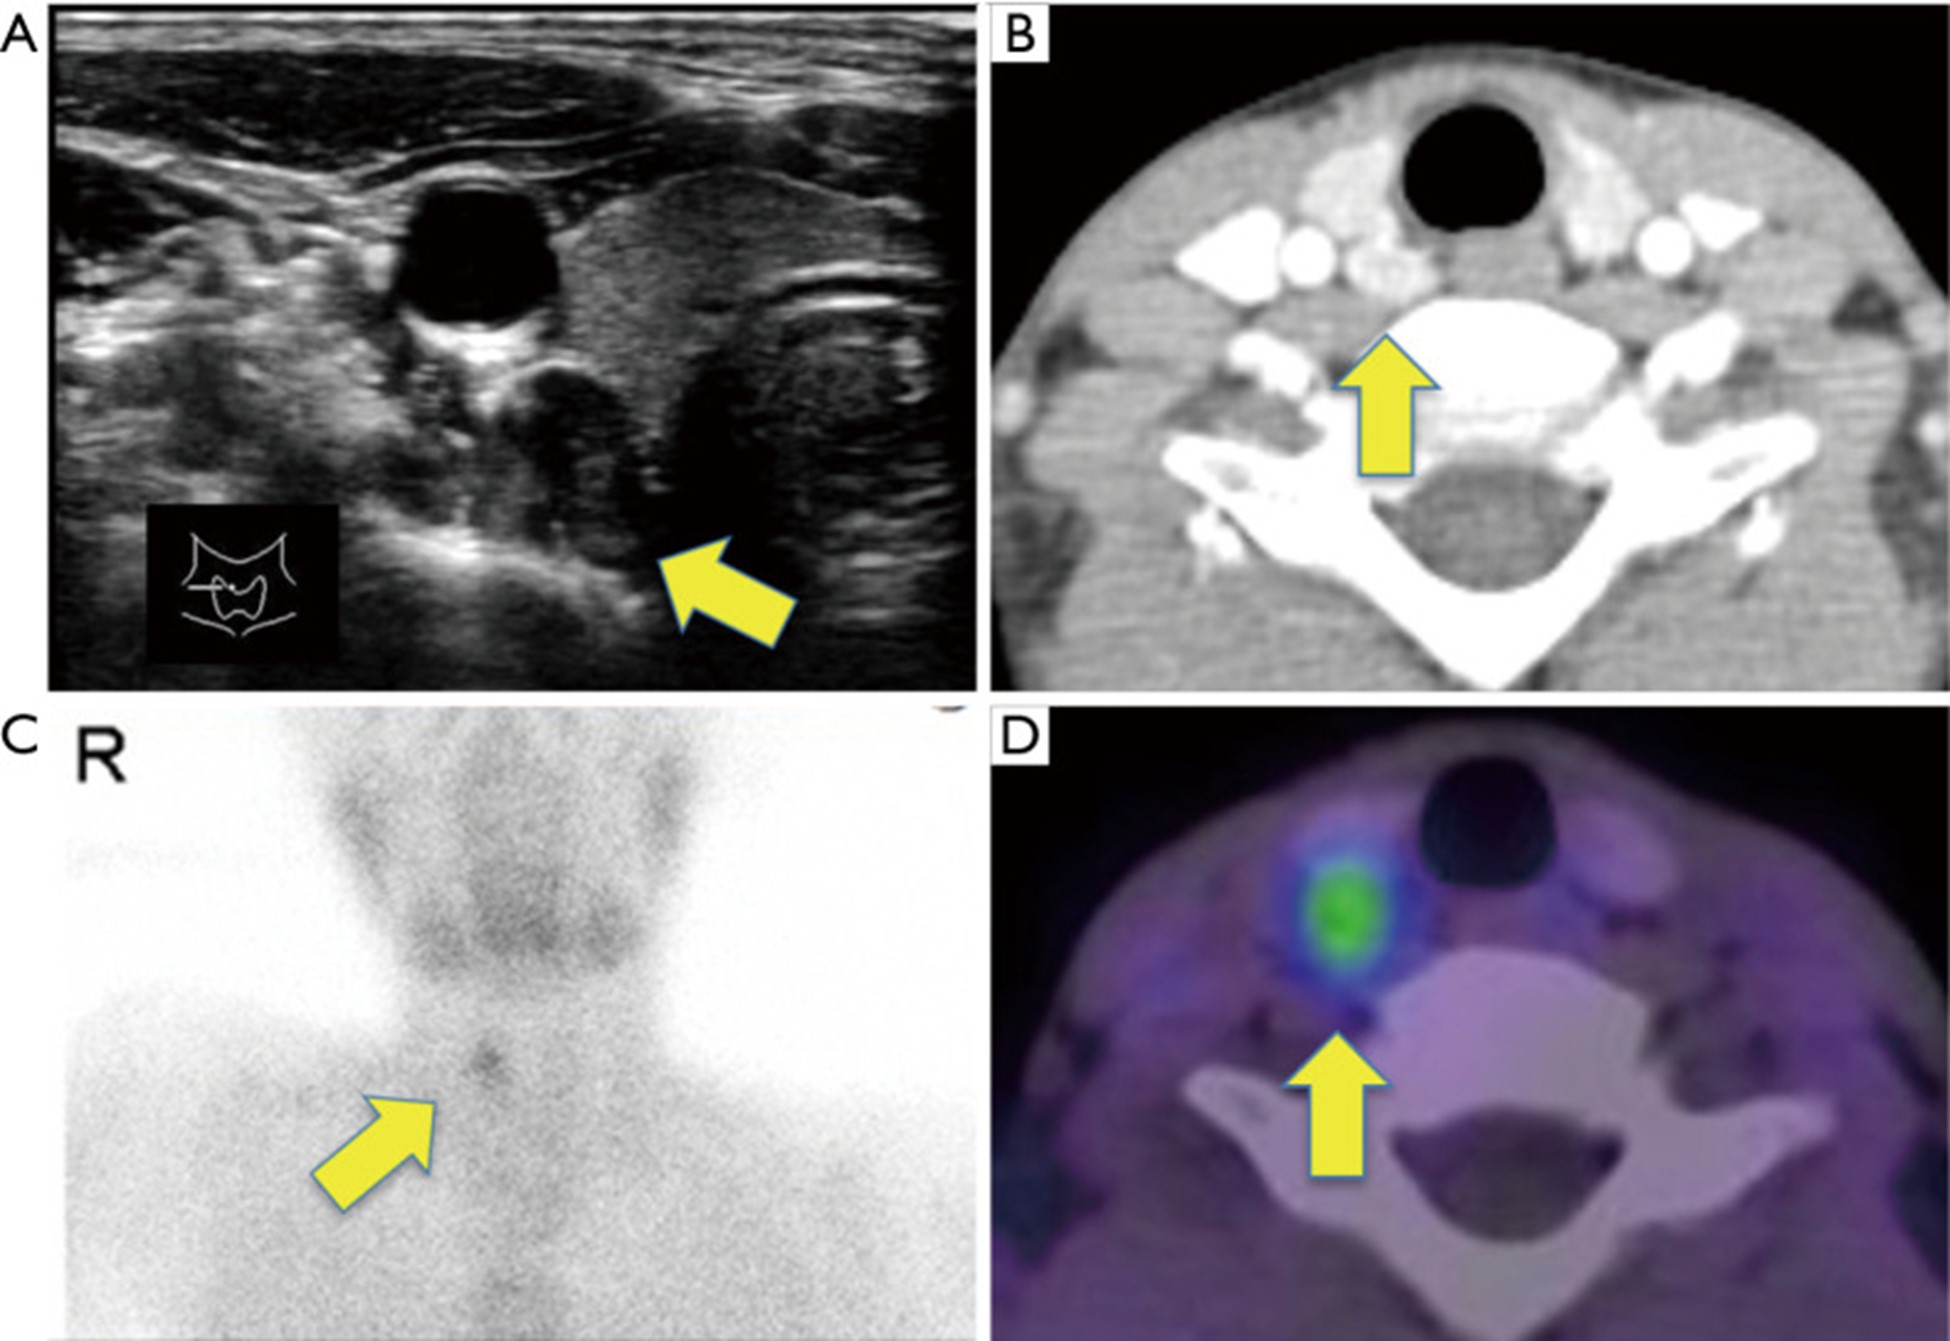

一名无严重疾病史或内分泌疾病家族史的 11 岁男孩因腹痛和恶心 3 个月到诊所就诊。进行了体格检查和血液检查。由于未检测血清钙,因此未发现高钙血症。随后,开始对症治疗。然而,他的症状恶化了。随后,男孩被送往附近医院接受进一步检查。血液化学检测显示白蛋白校正血清钙水平(14.3 mg/dL)显着升高(正常范围,8.7-10.2 mg/dL)和完整甲状旁腺激素(PTH)水平升高(405 pg/mL)(正常范围,10.0–65.0 pg/mL)。颈部超声检查显示甲状腺右叶背侧有一个大小为 15×9 毫米的明确肿块,图 1A)。对比增强计算机断层扫描还显示右上甲状旁腺增大(图 1B),这被认为是扩大的右上甲状旁腺。未检测到肾结石。Tc-99m sestamibi 闪烁显像显示与该肿块一致的积聚,没有检测到提示甲状旁腺的其他积聚(图 1C、1D)。他的腰骨矿物质密度为 0.682 g/cm 2,相对于他的年龄而言相对较低(一个 11 岁的日本男孩的正常范围:0.694–0.706 g/cm 2)。基于这些发现,他被诊断为原发性甲状旁腺功能亢进引起的高钙血症。立即开始治疗高钙血症,静脉输注生理盐水(2,400 mL/天)和速尿(60 mg/天)以促进钙排泄。患者还接受了降钙素(40 单位/天)。然而,高钙血症恶化(16.5 mg/dL),入院 2 天后出现严重恶心和全身乏力的高钙血症危象。由于这些症状,他几乎不能吃任何食物,变得昏昏欲睡。

图1:超声 (A)、对比增强计算机断层扫描 (B) 和 Tc-99m sestamibi 闪烁显像 (C,D) 发现。(A,B)在甲状腺右叶上极后发现一个 15×9 毫米的肿块(箭头),提示右上甲状旁腺肿大。(C,D)Tc-99m sestamibi 在该肿瘤中被摄取(箭头)。